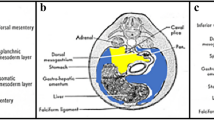

Posterior peritoneal reflections and recesses. Intraperitoneal fluid flows naturally from the pelvis to the upper abdomen. Flow occurs preferentially through the right rather than left paracolic gutters owing to the broader diameter of the right gutter. In addition, flow in the left paracolic gutter is cut off from reaching the left subphrenic space by the phrenicocolic ligament. The transverse mesocolon divides the abdomen into supra- and inframesocolic spaces. In the right inframesocolic space, fluid is impeded from draining into the pelvis via the small bowel mesentery. Owing to natural holdup of fluid at the root of the small bowel mesentery and sigmoid mesocolon, these structures are naturally predisposed to involvement with serosal-based metastases in the setting of peritoneal carcinomatosis (Reprinted with permission from Myers MA. Dynamic Radiology of the Abdomen: Normal and Pathologic Anatomy, New York: Springer, 1994)

Left (a) and right (b) perihepatic spaces. The left and right perihepatic spaces are bounded posteriorly by the coronary ligaments. The reflections of the coronary ligaments mark the site of the nonperitonealized “bare area” of the liver (LL left lobe of the liver, LK left kidney, S stomach, TC transverse colon, P pancreas, D duodenum, Lu lung, L liver [right lobe], A adrenal, K kidney, C colon) (Reprinted with permission from Myers MA. Dynamic Radiology of the Abdomen: Normal and Pathologic Anatomy, New York: Springer, 1994)